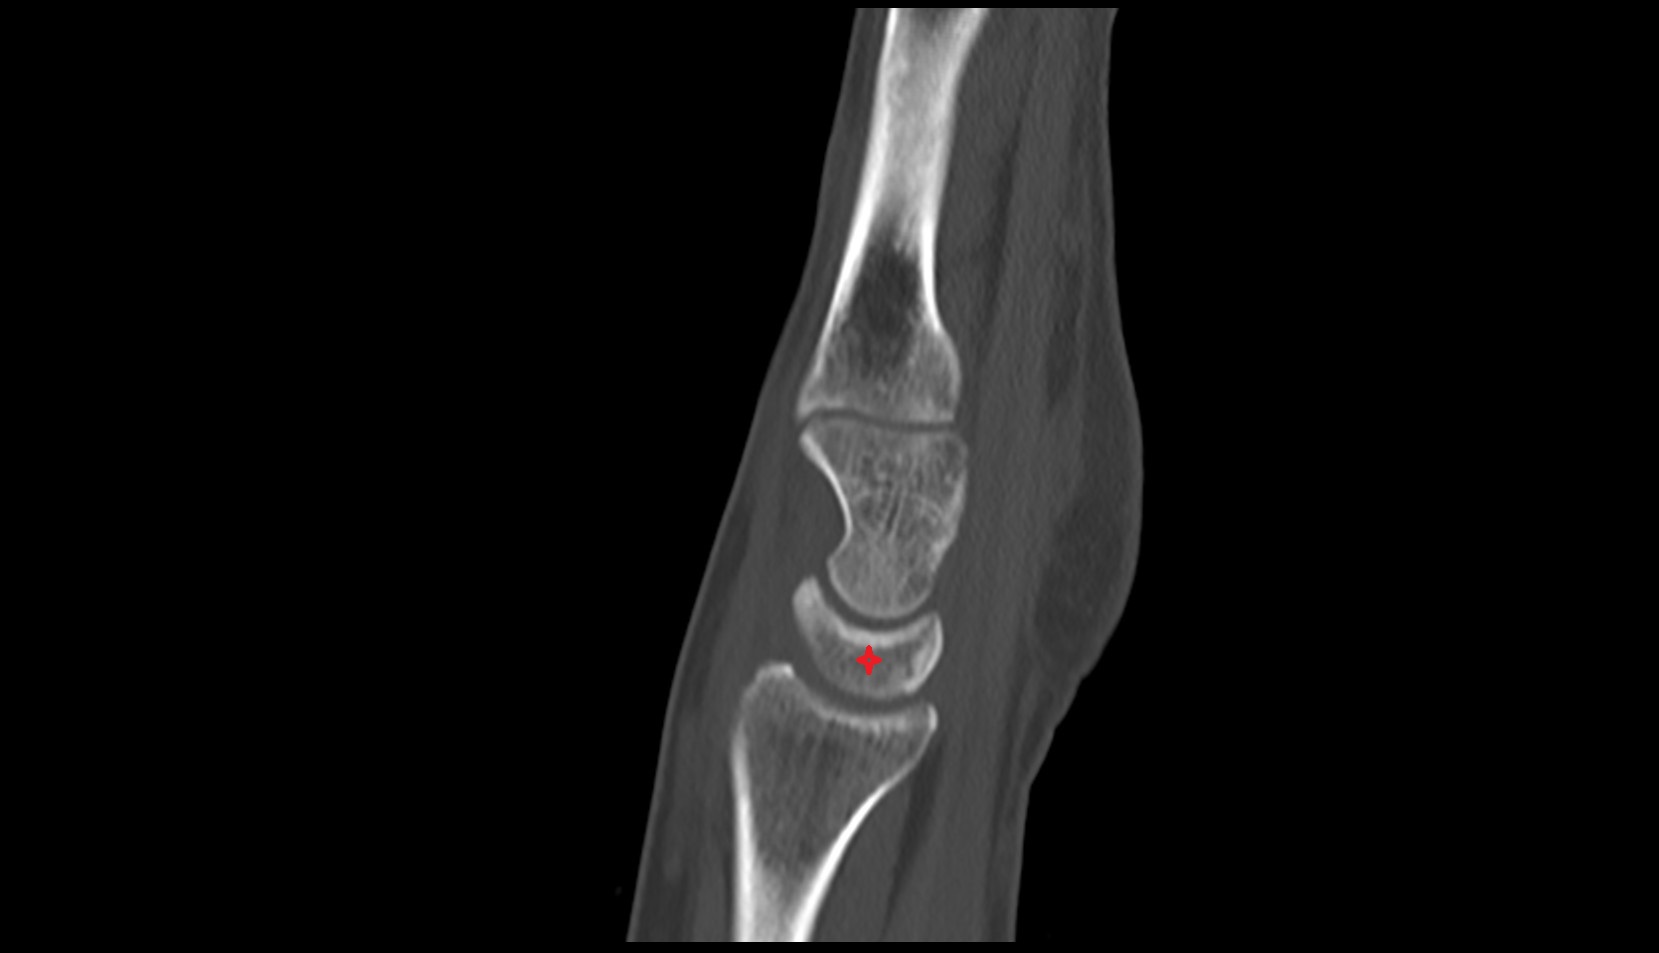

- Elbow joint